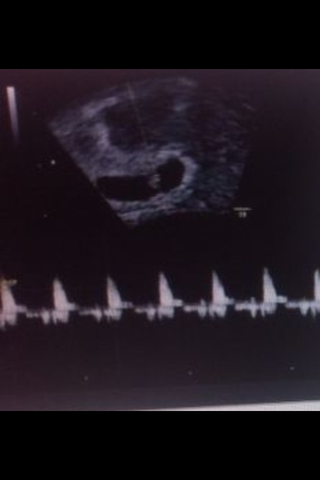

Su corazón late con una medida de 150 pulsaciones por minuto

Ya se escuchan los latidos del bebe

su corazon palpita 120-160 pulsaciones por minuto